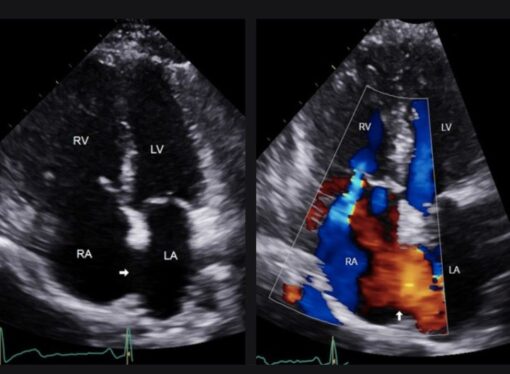

The following study presents data confirming that obstructive sleep apnea syndrome (OSAS) is associated with an increased number of cardiovascular abnormalities detectable by echocardiography, underscoring the need for routine cardiovascular screening in patients with OSAS. Given the systemic implications of OSAS beyond sleep disturbances, a multidisciplinary approach is essential for early diagnosis and optimized management, with the goal of mitigating cardiovascular risk and improving outcomes. OSAS is a significant cardiovascular risk factor requiring comprehensive clinical care.